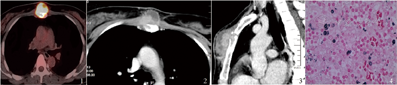

患者 女,36岁。前胸壁(近胸骨角处)肿物、疼痛2个月,曾口服抗生素未见明显好转,肿物呈增大趋势。胸部CT检查示:胸骨角前肿物并骨质破坏。查体:肿物位于胸骨前方,大小约5 cm×5 cm×4 cm,质硬,推之不动,周围边界清,皮肤周围未见明显炎症改变,瘤体顶部约有1 cm×1 cm软化区。患者术前HIV、结核菌素试验、血结核DNA、CEA、CA199等相关检查结果均为阴性。全身PET/CT检查示:胸骨体前肿物明显放射浓聚并骨质破坏(SUV max值:17.1),无明显远处转移。患者既往无外伤史,近期无禽鸟密切接触史。

2017年6月行肿物切除术。术中见肿物侵犯胸骨皮质,呈溶骨破坏为主,部分深达骨髓质。切开肿物见内有脓液流出,呈类似"干酪样"改变。术后病理结果示:肿物呈慢性肉芽肿性炎,六胺银染色(+),PAS-AB染色(弱+)的球形结构,考虑新型隐球菌。抗酸染色(-)。术后颅脑MRI检查未见颅内感染征象。每日口服大扶康400 mg,治疗12周[1]。